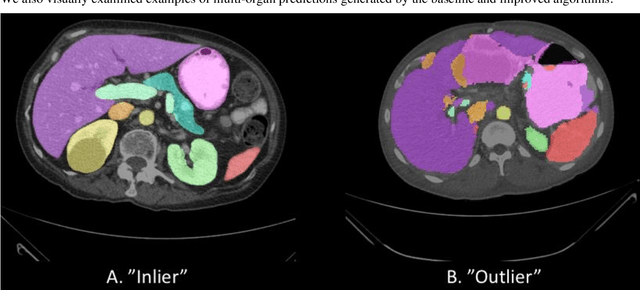

Abstract:Abdominal multi-organ segmentation of computed tomography (CT) images has been the subject of extensive research interest. It presents a substantial challenge in medical image processing, as the shape and distribution of abdominal organs can vary greatly among the population and within an individual over time. While continuous integration of novel datasets into the training set provides potential for better segmentation performance, collection of data at scale is not only costly, but also impractical in some contexts. Moreover, it remains unclear what marginal value additional data have to offer. Herein, we propose a single-pass active learning method through human quality assurance (QA). We built on a pre-trained 3D U-Net model for abdominal multi-organ segmentation and augmented the dataset either with outlier data (e.g., exemplars for which the baseline algorithm failed) or inliers (e.g., exemplars for which the baseline algorithm worked). The new models were trained using the augmented datasets with 5-fold cross-validation (for outlier data) and withheld outlier samples (for inlier data). Manual labeling of outliers increased Dice scores with outliers by 0.130, compared to an increase of 0.067 with inliers (p<0.001, two-tailed paired t-test). By adding 5 to 37 inliers or outliers to training, we find that the marginal value of adding outliers is higher than that of adding inliers. In summary, improvement on single-organ performance was obtained without diminishing multi-organ performance or significantly increasing training time. Hence, identification and correction of baseline failure cases present an effective and efficient method of selecting training data to improve algorithm performance.